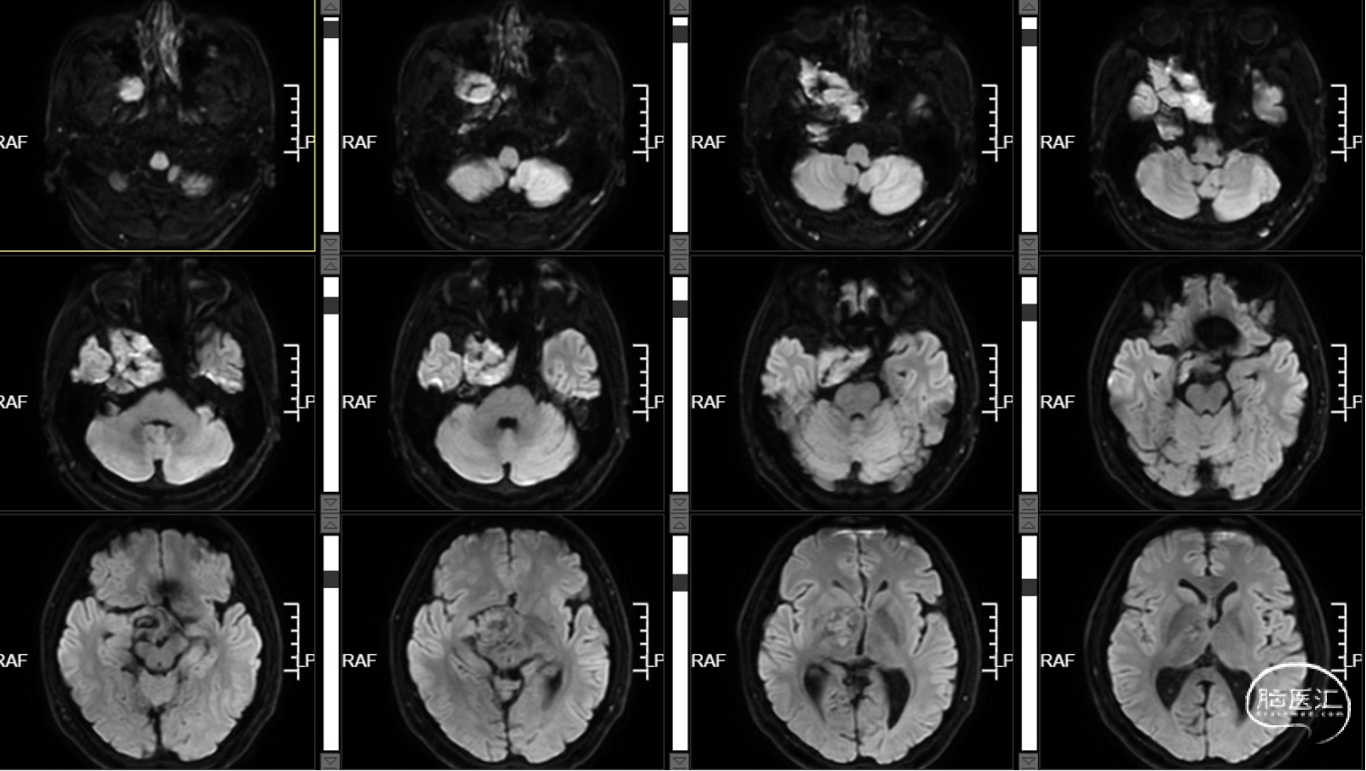

外院MR示:右侧颞底、桥小脑角区及鞍内占位,考虑表皮样囊肿伴破裂可能。